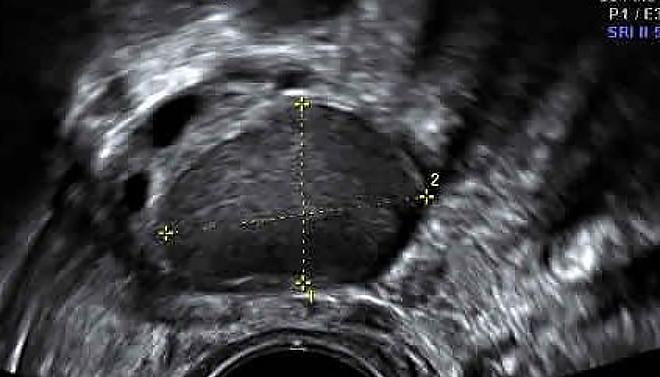

Как выглядит киста яичника на УЗИ

Главным признаком кисты яичника при ультразвуковом исследовании является образование полого отростка на его поверхности. В отличие от нормального фолликула, который изменяется в течение менструального цикла, киста остается неизменной. Кроме того, такое образование обычно имеет больший размер.

На ультразвуковом снимке киста яичника отображается в виде черного пятна, размеры которого варьируются от 3 до 20 см.

Киста желтого тела

Это округлая, гипоэхогенная структура с толстыми стенками. Полость кисты четкая и гладкая, без каких-либо включений.

Обычно размер кисты желтого тела составляет от 4 до 8 см. Благодаря наличию пристеночного кровотока, на ультразвуковом исследовании она выглядит как огненное кольцо.